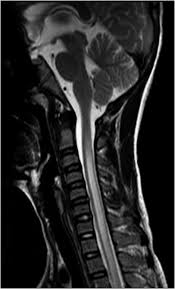

Case Record Idiopathic Postinfectious Transverse Myelitis from image.slidesharecdn.com Jan 14, 2017 · transverse myelitis is an inflammatory condition of the spinal cord associated with rapidly progressive neurologic dysfunction. G37.3 acute transverse myelitis in demyelinating disease of central nervous system g37.4 subacute necrotizing myelitis of central nervous system g37.5 concentric sclerosis balo of central nervous system g37.8 other specified demyelinating diseases of central nervous system g37.9 demyelinating disease of central nervous system, unspecified Transverse myelitis postsurgical spine avm brachial plexus post radiation therapy, eval for mass lesions, entrapment, denervation cervical spine w and w/o contrast 72156 thoracic disc disease pain radiculopathy trauma thoracic spine w/o contrast 72146 tumor infection ms syrinx transverse myelitis postsurgical spine avm They most commonly affect elderly men and are classically found in the thoracolumbar region. As part of a health sciences university, baylor medicine in houston, texas puts the latest treatments, innovations, and therapies in the hands of its highly trained doctors and care teams, who are working together to develop and deliver a care plan personalized for you. In the acute setting, there is often associated contrast enhancement. Rare neurological complications include transverse myelitis and/or cauda equina syndrome 20, 21; Compression of the upper spinal cord, multiple sclerosis, transverse myelitis, behçet's disease, osteogenesis imperfecta lhermitte phenomenon , also called the barber chair phenomenon , is an uncomfortable electrical sensation that runs through the back and into the limbs.

In the acute setting, there is often associated contrast enhancement. G37.3 acute transverse myelitis in demyelinating disease of central nervous system g37.4 subacute necrotizing myelitis of central nervous system g37.5 concentric sclerosis balo of central nervous system g37.8 other specified demyelinating diseases of central nervous system g37.9 demyelinating disease of central nervous system, unspecified They most commonly affect elderly men and are classically found in the thoracolumbar region. Transverse myelitis postsurgical spine avm brachial plexus post radiation therapy, eval for mass lesions, entrapment, denervation cervical spine w and w/o contrast 72156 thoracic disc disease pain radiculopathy trauma thoracic spine w/o contrast 72146 tumor infection ms syrinx transverse myelitis postsurgical spine avm Compression of the upper spinal cord, multiple sclerosis, transverse myelitis, behçet's disease, osteogenesis imperfecta lhermitte phenomenon , also called the barber chair phenomenon , is an uncomfortable electrical sensation that runs through the back and into the limbs. Jan 14, 2017 · transverse myelitis is an inflammatory condition of the spinal cord associated with rapidly progressive neurologic dysfunction. As part of a health sciences university, baylor medicine in houston, texas puts the latest treatments, innovations, and therapies in the hands of its highly trained doctors and care teams, who are working together to develop and deliver a care plan personalized for you. Rare neurological complications include transverse myelitis and/or cauda equina syndrome 20, 21; The av shunt is located inside the dura mater close to the spinal nerve root where the arterial blood from a.